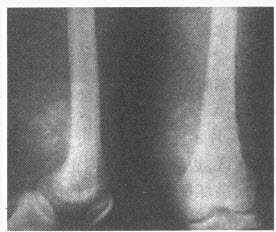

女,60岁,左肘关节肿痛1年余,局部无红肿。左肘关节活动受限。结合左肘关节正侧位片,应诊断为()

A:类风湿性关节炎

B:滑膜骨软骨瘤病

C:关节结核

D:神经营养性关节病(Charcot关节)

E:色素沉着绒毛结节性滑膜炎